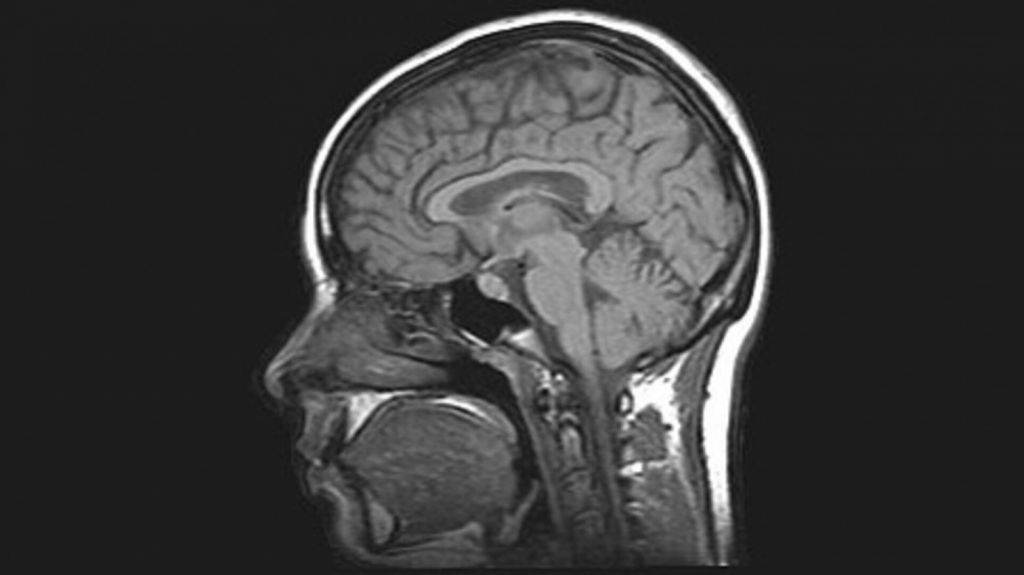

Επικαιρότητα Αυτές είναι οι πέντε εποχές του εγκεφάλου, σύμφωνα με τους επιστήμονεςΜία από τις πιο εκτεταμένες επιστημονικές έρευνες για την εξέλιξη του ανθρώπινου εγκεφάλου εντόπισε πέντε κύριες «εποχές» ανάπτυξης, χαρτογραφώντας πώς αλλάζει η νευρωνική συνδεσιμότητα από τη βρεφική ηλικία έως τα βαθιά γηρατειά. Η μελέτη, που βασίστηκε σε εγκεφαλικές απεικονίσεις σχεδόν 4.000 ατόμων ηλικίας από μερικών μηνών έως 90 ετών, κατέγραψε τις μεταβολές των νευρικών συνδέσεων […] 25/11/2025 13:03